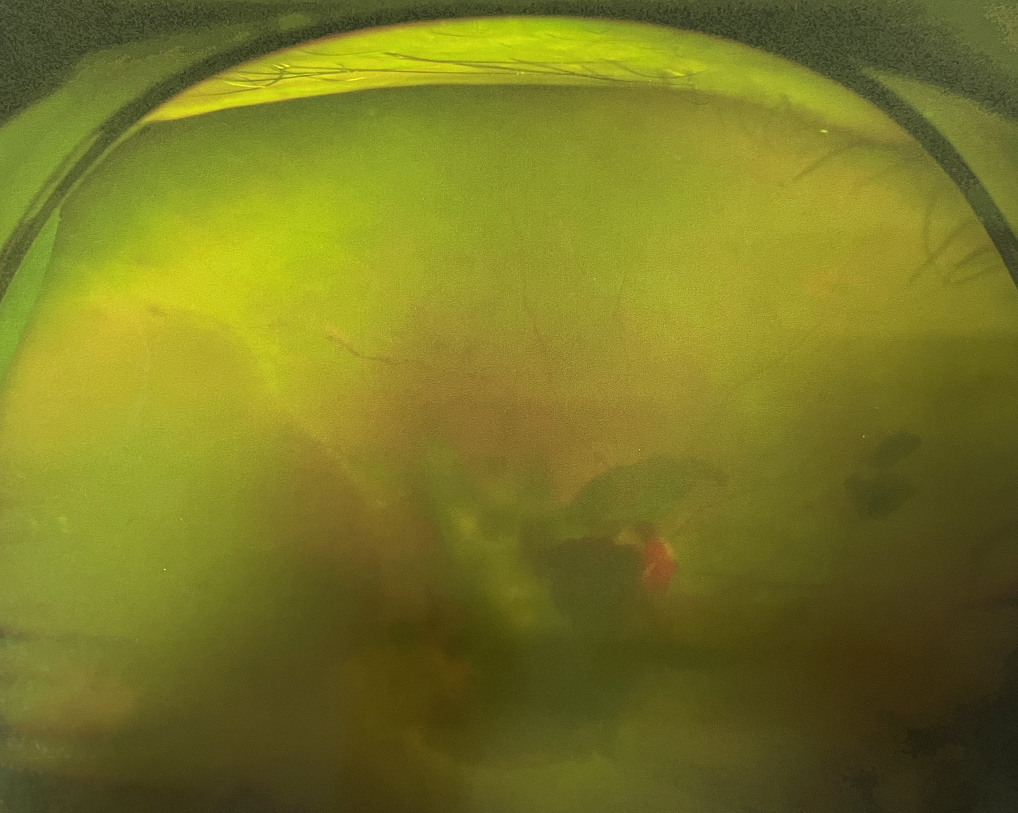

眼底出血是指眼內(nèi)視網(wǎng)膜出血,或玻璃體內(nèi)出血。眼底位于眼睛深處,所以這類出血只靠肉眼是看不到的,早期可能不紅、不痛、不癢,需通過專業(yè)的眼底檢查才可看到,往往短期內(nèi)就可造成視力驟降甚至失明!

同樣的,眼底出血也是一種癥狀,而非病種。誘發(fā)眼底出血的原因很多,常見的有全身性血管病和血液病、視網(wǎng)膜血管異常、機(jī)械性阻塞、炎癥性疾病或免疫復(fù)合物侵犯血管壁等。